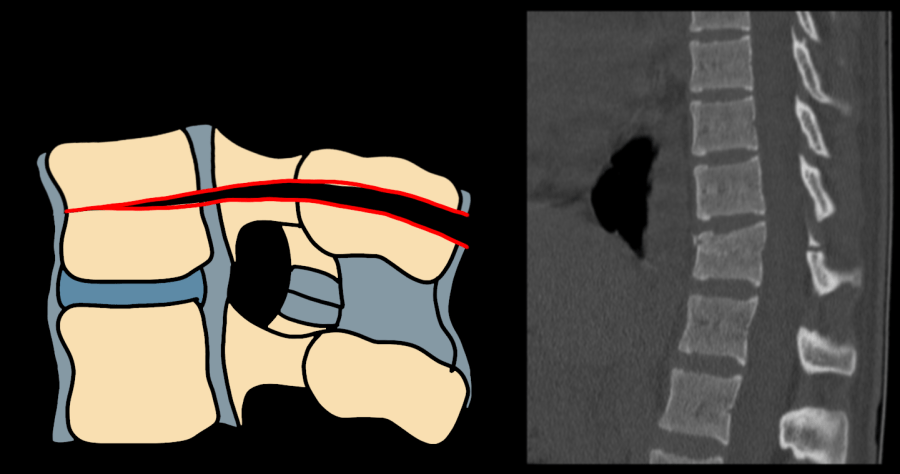

AO Type C fracture-dislocation — CT sagittal and coronal showing complete translational displacement of the spinal column

Type C — fracture-dislocation; complete translational instability